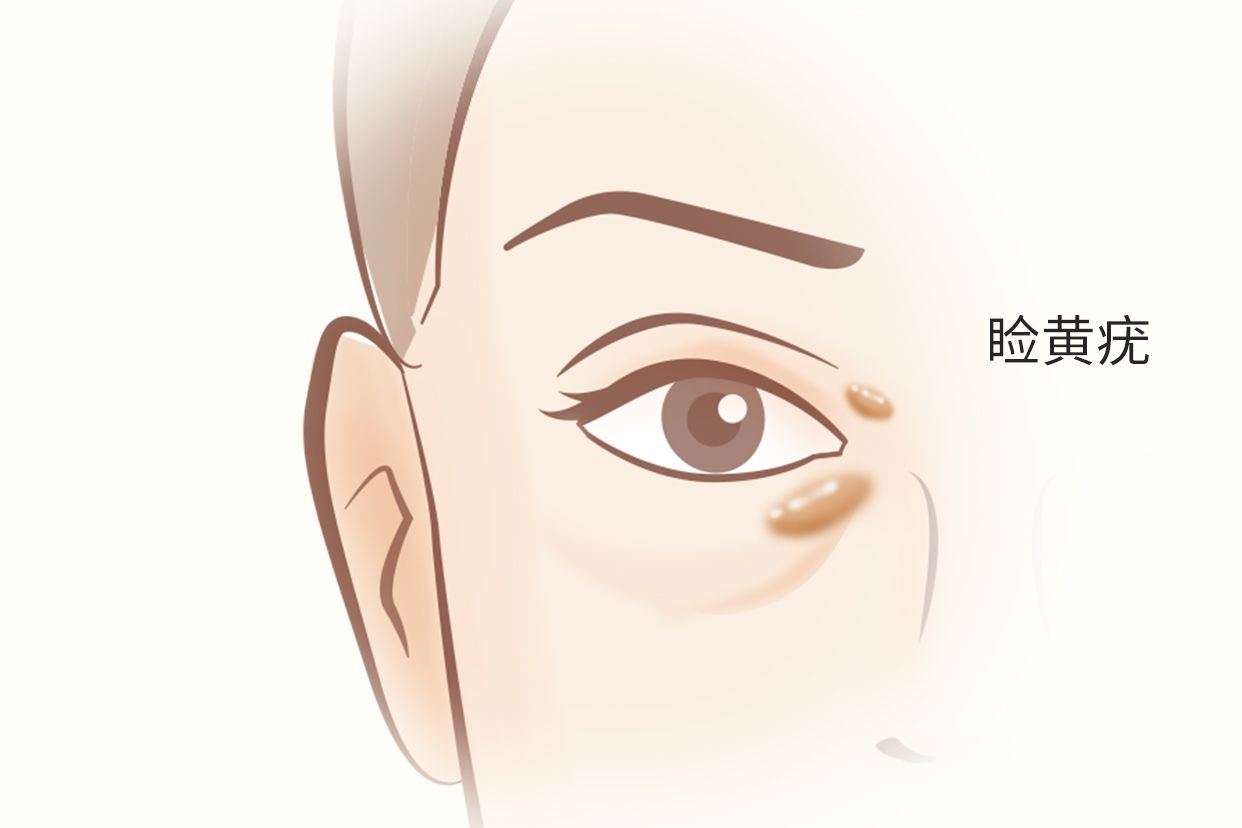

睑黄疣,是一种与代谢障碍有关的皮肤疾病。患者初期上睑会出现扁平的黄色斑点,稍微凸起,常发生于双侧内眦。建议患者及时查明病因,遵医嘱采用药物及激光等进行治疗。

睑黄疣是单个或数个黄色小斑点逐渐变大,隆起和融合,呈圆形或椭圆形,可围绕内眦形成马蹄形或不规则形状,但不超出眶周,一般为米粒至蚕豆大小,无自觉症状,发展缓慢,不能自行消退。